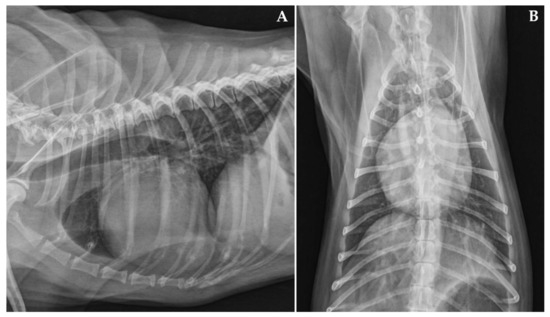

Case Description and Clinical Investigations